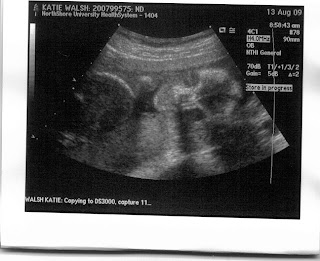

And here he is... Yes, I said he!!! It's another boy!!!

The ultrasound tech said he's biting his nails, but I prefer to think he's sucking on his hand and he's going to be a self-soother (so we won't have to ever think of taking away another child's pacifier again!)

Cute little feet (that just love to kick my bladder!)

Skeleton baby profile.